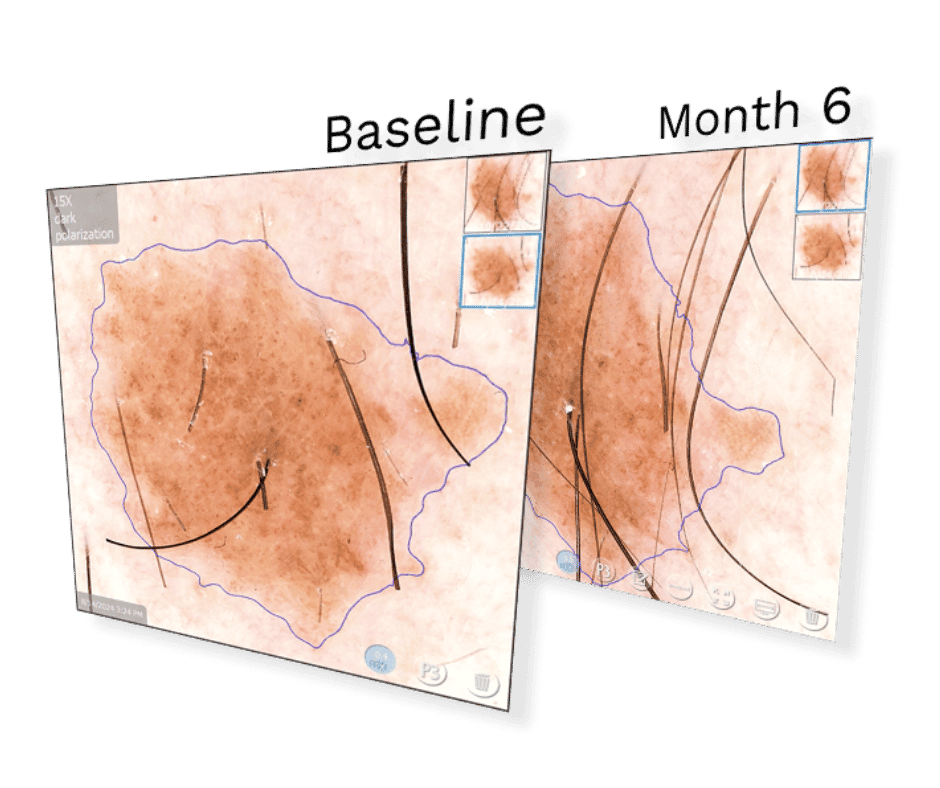

- Automatic change detection between visits

- Digital record for precise tracking over time